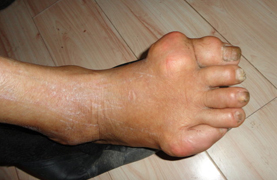

【易发部位】脚拇指关节、拇趾跖关节、跗跖关节、踝关节、手指关节,掌指关节、腕关节、肘关节、膝关节、耳廓。

【典型症状】膝肿痛、关节痛、关节肿胀、尿酸高、发热、厌食、鹤膝风。